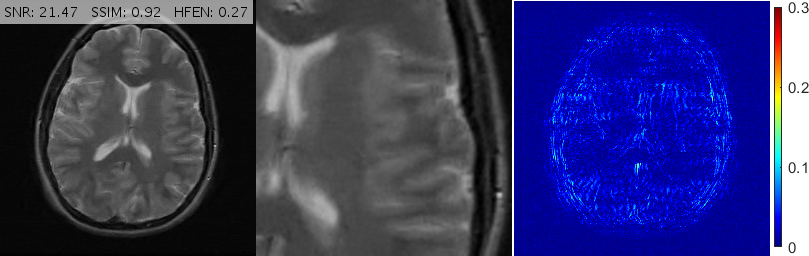

Fig. 10 shows the performance of various algorithms for a sagittal head scan reconstruction under 16% spiral sampling. The solutions provided by pFISTA and TL miss much of the image content due to over-smoothing. TGV+Shearlet leaves many incoherent artifacts on all regions. The magnified views obviously show that BM3D degrades the image by leaving block artifacts around the cerebellum and streaking artifacts on the medulla and the visual cortex. DAMP, GBRWT, ADMM Net and FDLCP provide more accurate results, however, by inspecting the magnified views it becomes evident that some small artifacts are introduced in DAMP near the caudate nucleus and beneath the cerebellum while a dark hole at the center of the cerebellum has been almost entirely smoothed out by the other three methods. The proposed method (labeled ‘New’) accurately captures this hole and corrects all the errors mentioned above.

Fig. 13 demonstrates various reconstructions for an axial -weighted brain image under a 20% Cartesian sampling. The magnified views show that FDLCP has smoothed out fine cerebral details while DAMP, ADMM Net, GBRWT, pFISTA, TL and TGV+Sh have introduced severe artifacts into the image, not least among them is a very large dark hole in the parietal lobe. BM3D provides a better result but this method also degrades the ventricles. The proposed framework again gives the best result with the cleanest error map.

For convenience, in Figs. 10, 11 and 13 we have inserted the SNR, SSIM and HFEN values for each method to the top of the corresponding reconstructed image. Moreover, some reconstruction errors in compared methods and their corrections in the proposed method are annotated with arrows.